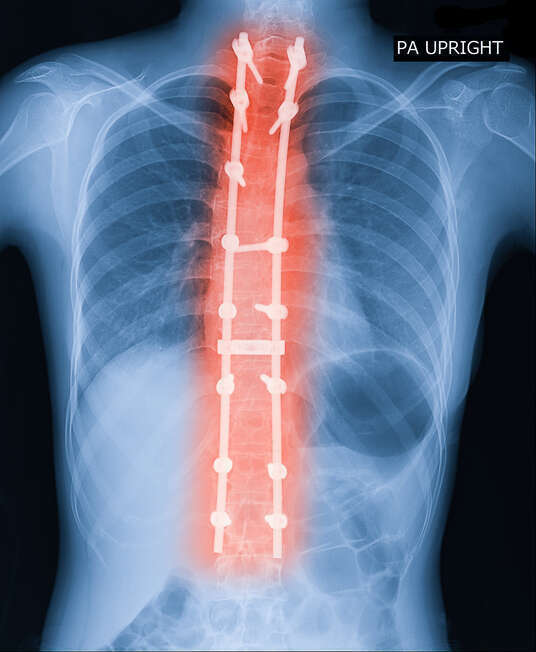

Grâce à un examen orthopédique, neurologique, postural, ainsi qu'une analyse précise des radiographies de votre colonne vertébrale grâce au logiciel Posture-ray, nous posons un "état des lieux" précis et vous proposons une prise en charge personnalisée.

J'ai trouvé le centre du Docteur Legagnoux suite à une recherche sur internet relative à une scoliose. Dès le 1er RDV, le Dr Legagnoux explique de façon claire et précise la démarche qu'il suit. A partir de radios spécifiques à la problématique, il montre les écarts entre la posture attendue et notre posture actuelle. Basée sur des données précises, il donne des explications et détaille ce qui peut être possible, proposant ainsi le protocole adapté et débute les traitements. C'est un très bon professionnel. L'équipe qui travaille avec lui est également très accueillante et attentionnée. Merci (Translated by Google) I found Dr. Legagnoux's clinic after an internet search related to scoliosis. From the very first appointment, Dr. Legagnoux clearly and precisely explained his approach. Using X-rays specific to the problem, he showed the discrepancies between the desired posture and our current posture. Based on precise data, he provided explanations and detailed what was possible, proposing a suitable protocol and beginning treatment. He is a very good professional. The team that works with him is also very welcoming and attentive. Thank you.

Je suis en cours de traitement par tractions pour une hypercyphose dorsale et une déviation de la colonne cervicale qui me provoquent des crises de douleurs dans les trapèzes et des névralgies d’Arnold. Les radios pratiquées toutes les 20 séances montrent que ma colonne s’améliore progressivement, l’intensité de mes crises a diminué et ma posture s’est améliorée. Je continue donc ce traitement qui est très efficace et le recommande vivement, d’autant plus que toute l’équipe est très professionnelle et l’ambiance sympathique et chaleureuse. (Translated by Google) I am currently undergoing traction therapy for hyperkyphosis of the thoracic spine and cervical spine deviation, which cause me episodes of pain in my trapezius muscles and Arnold's neuralgia. X-rays taken every 20 sessions show that my spine is gradually improving, the intensity of my attacks has decreased, and my posture has improved. I am therefore continuing this treatment, which is very effective, and highly recommend it, especially since the entire team is very professional and the atmosphere is friendly and welcoming.